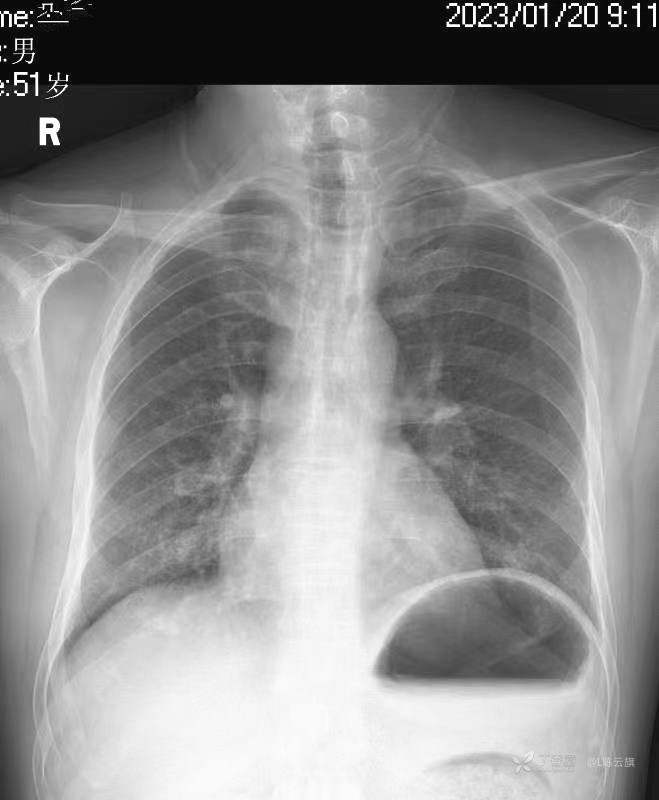

华夏览雄 达人已点赞1、患者男,51岁,精神病长期住院患者,主要病史只有时不时觉得腹部不适,其他不详。系列胸片为定期胸部检查。

3、根据系列复查胸、腹部平片的不同表现,你能否总结出什么征象和经验呢?